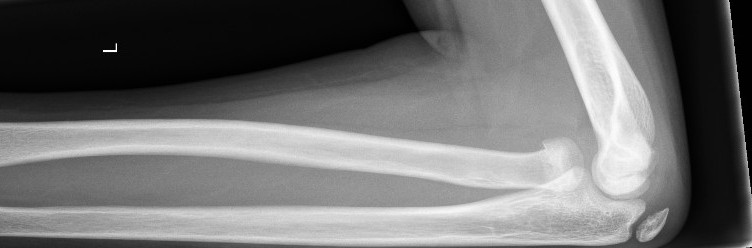

Radial Head and Neck Fractures (Proximal Radius)

- Minimally displaced radial head and neck fractures with < 30 degrees angulation

- Above elbow plaster backslab at 90 degrees flexion with Orthopaedic Fracture clinic follow up in 7-10 days.

- Displaced fractures or > 30 degrees angulation

- should be discussed with the Orthopaedic team for reduction.

Radial neck fracture